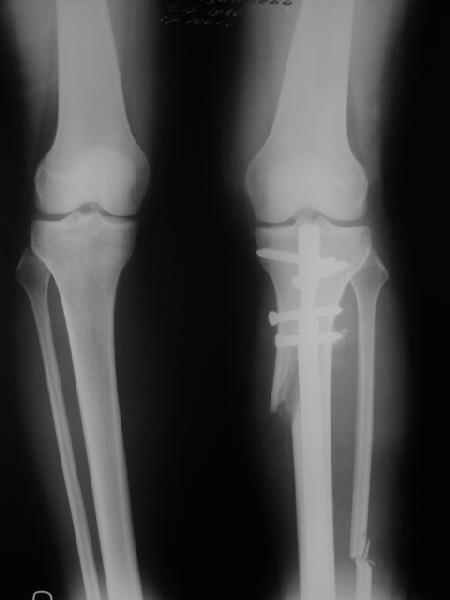

. On the right leg you can see some of the tools (from the tool bar above) applied to demonstrate a mild mech-axis varus of about 5 degrees.

On the left the bone landmarks used in the anlaysis are shown.

In essence she has a mild mech-axis varus of 7 degrees with some contribution from the femur (2) degrees and more from the tibia (6 degrees), none from the joint.

Yesterday i performed correction of one leg (the plan to make both in one session was cancelled because of some external reasons). Suggestions of Nuno Lopes were most close to my view. A small wire distractor was used intraoperatively. Derotation ~6-7 degrees was performed also. CT scans evaluating rotation will be available only

tomorrow. No problem to change rotation of the operated limb in the moment of the second surgery. Comments/critics are welcome.

Can the attached result be analyzed by the software?